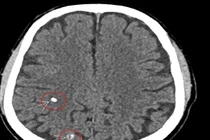

Thiếu máu não là bệnh phổ biến gây hoa mắt, đau đầu, chóng mặt... nên chúng ta thường thờ ơ, chủ quan mà không biết biến chứng nặng, nguy hiểm cho tính mạng và sức khỏe. Vì vậy, cần chú ý.

Cơn thiếu máu não thoáng qua có triệu chứng kéo dài từ vài phút đến vài giờ. Tuy nhiên, cơn thiếu máu não thoáng qua được xem là một trong những cảnh báo đột quỵ sắp xảy ra.